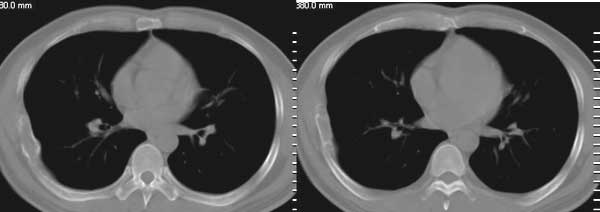

房**,38岁,间歇性胸疼2年

肋骨溶骨性破坏,皮质膨胀呈囊状,可见间隔,部分边缘硬化。考虑肋骨骨纤维结构不良。

膨胀性肋骨破坏,皮质连续。周围软组织无异常。良性占位。首先考虑骨纤。

膨胀性骨破坏,骨皮质尚完整.周围软组织脂肪间隙清楚.

膨胀性改变,皮质不连,周围软组织未见异常,考虑骨纤